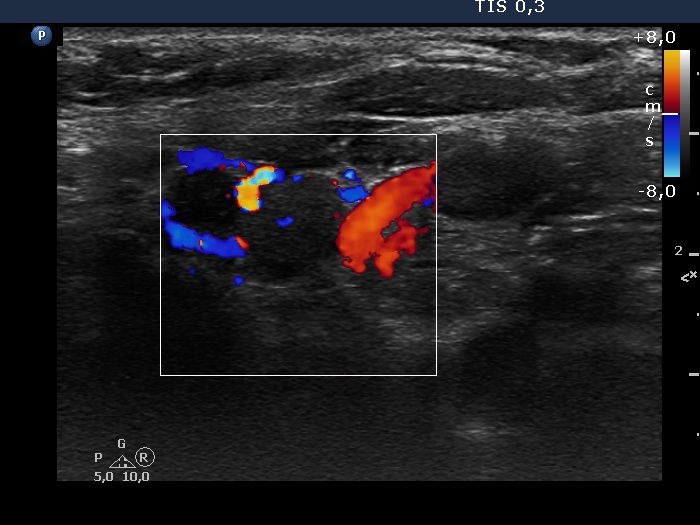

Lower part of the left lobe, transverse scan, color Doppler mode.